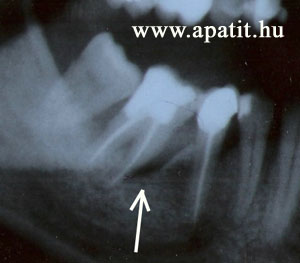

Az alsó nagyőrlő elülső gyökerénél gyökércsúcsig érő csonttasak. A fogat eltávolítottuk.